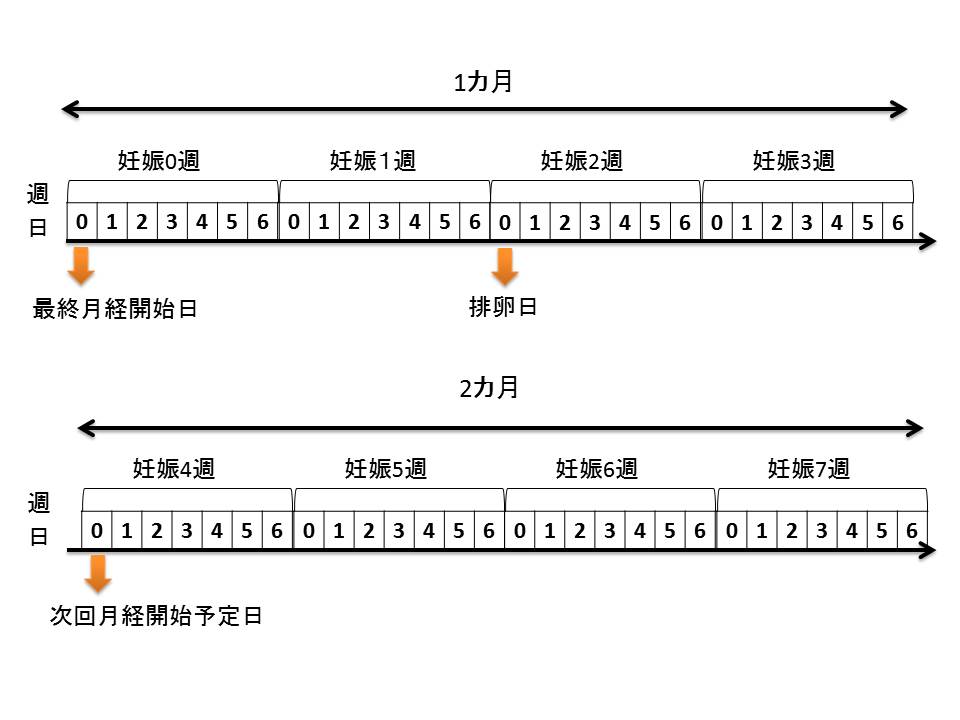

妊娠2カ月 妊娠4週 7週 ごろのお母さんの体調の変化 はぐふる

妊娠2カ月 妊娠4 7週 ベビーカレンダー

妊娠初期 1 4か月 2か月 4 7週 妊娠期 育児期カレンダー まめコミ

妊娠2カ月 妊娠4週 7週 ごろのお母さんの体調の変化 はぐふる

妊娠初期 1 4か月 2か月 4 7週 妊娠期 育児期カレンダー まめコミ